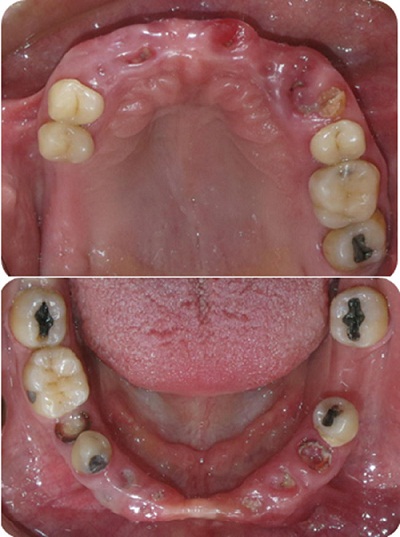

En el examen clínico, se evidenciaba en la paciente una lesión asintomática en el lado izquierdo del labio superior, con afectación de bermellón y epitelio de mucosa. La lesión era dura a la palpación, tenía un diámetro de 1,5 cm, era delimitada por la lesión tipo placa y mostraba múltiples erosiones de color rojizo y costra. No se encontraron linfoadenopatías asociadas (figura 1). También mostraba fisuras palmoplantares (figura 2) y múltiples carcinomas basocelulares en la espalda y el dorso de la mano izquierda (figura 3).

No se encontraron lesiones en el examen intraoral. La paciente era edéntula parcial con desarmonía oclusal sin previo tratamiento de rehabilitación (figura 4). Radiográficamente, se encontraron múltiples espacios edéntulos, múltiples restos radiculares en la zona anterior de los maxilares superior e inferior, calcificación del ligamento estilohioideo y ausencia de queratoquistes mandibulares que pudieran asociarse con el síndrome de Gorlin-Goltz (figura 5).